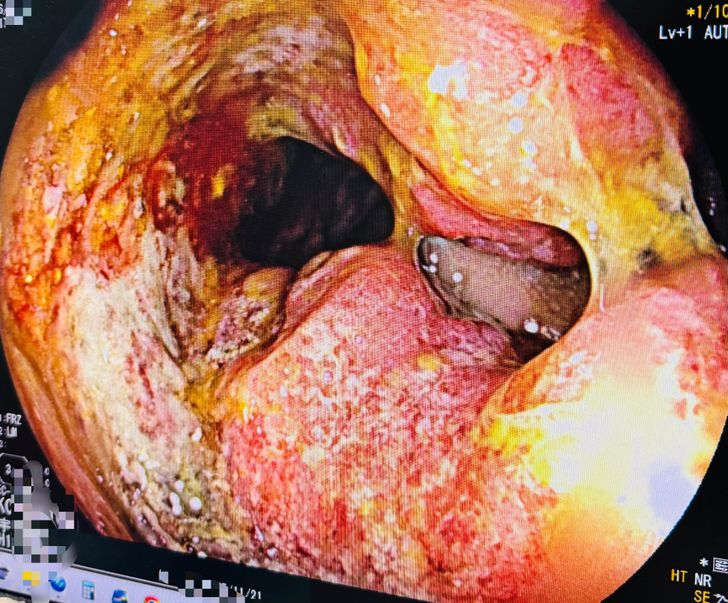

ผลตรวจออกมาน่าตกใจกว่าที่คิด พบก้อนเนื้อมะเร็งขนาดใหญ่ที่ลำไส้ตรง (Rectum) ซึ่งอุดกั้นทางเดินอาหารจนเกือบมิด เป็นสาเหตุที่ทำให้ถ่ายไม่ออกมาตลอด